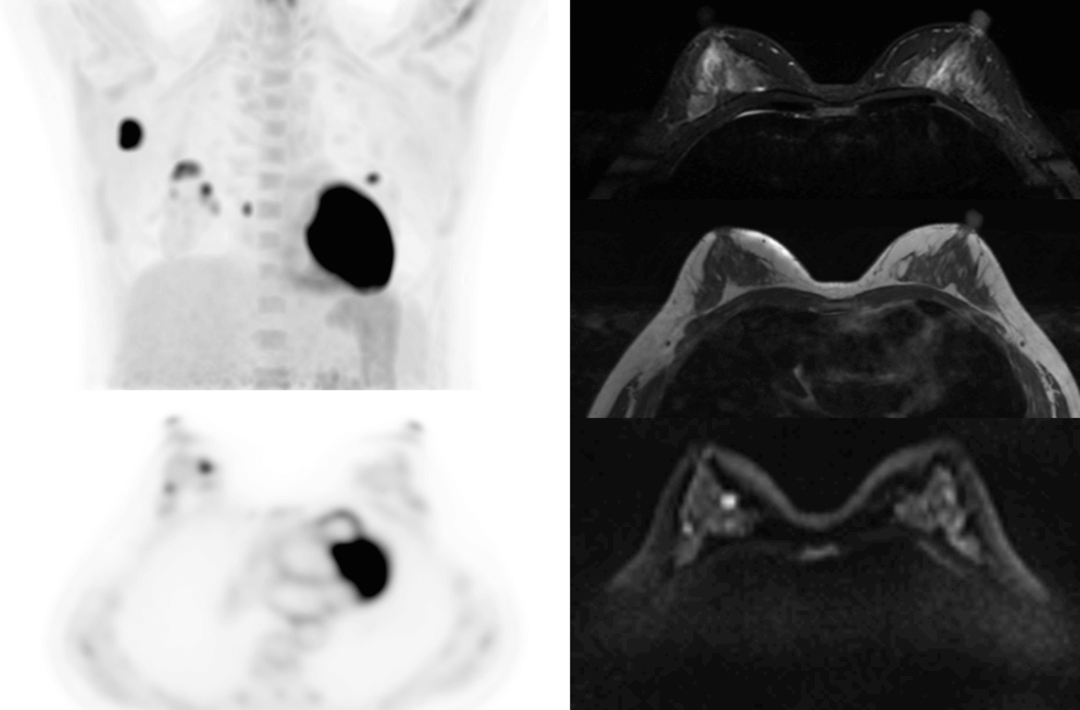

PET/MRは分子機能と構造画像を完全に結合し、腫瘍、心血管疾患、神経疾患、小児疾患、炎症性疾患の臨床診断に欠かせない手段として役立っています。

AFOVが、従来の20cm~25cmのPET装置と比較して、32cmの長尺AFOVであることにより、感度が向上するだけでなく、全身の主要臓器や転移が考えられる局所リンパ系において1ベッドポジションでがんのTNステージを実現することが可能となります。

従来、腫瘍系のPET/MR撮影には約35~50分かかっていました。長いAFOVは、PET/MRの腫瘍スキャン方式をさらに最適化することができます。局所PET/MRスキャン後に腫瘍の局所リンパ転移の有無に基づいて全身をスキャンするかどうかの判断を最適化でき、転移のない患者さまのスキャン時間を短縮できる可能性があります。

乳がん、食道がん、前立腺がんなどのTNMステージングを「時空間統合」ULTRA-clear TOF PET/MRの長軸視野で最適化した事例を紹介します。